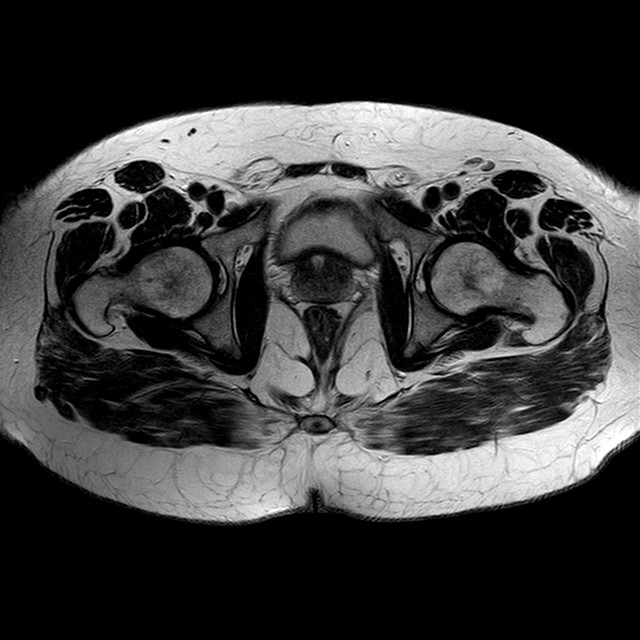

Esami: RMN BACINO

eT2w TSE

Evidenti e simmetriche alterazioni osteofitosiche in regione coxo femorale con riduzione delle rime articolari. Degenerazione completa del cercine glenoideo. Non attuali segni di versamento articolare. Non segni di edema osseo che escludono attuale algodistrofia od osteonecrosi. Lieve e simmetrica riduzione del trofismo della muscolatura glutea.